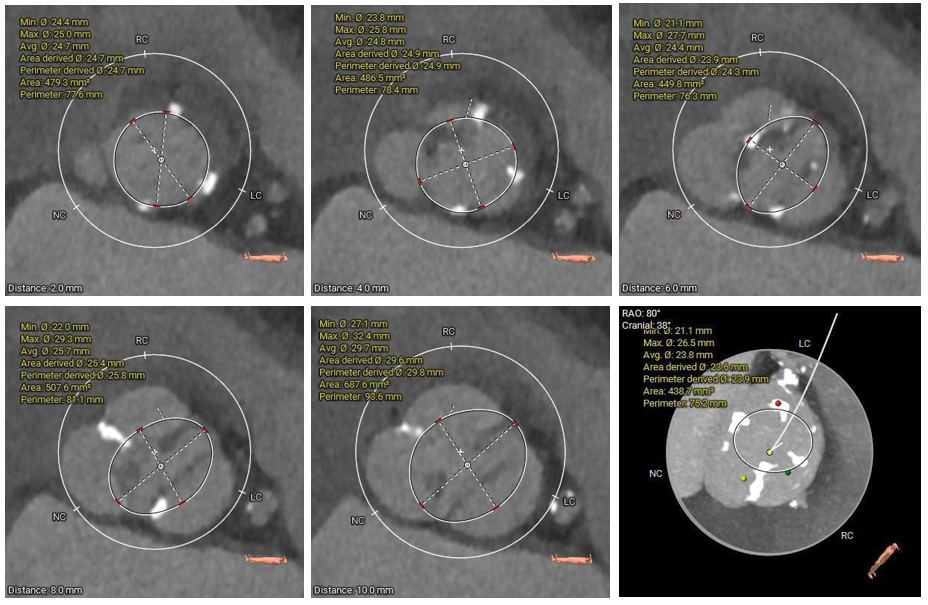

主动脉根部测量

瓣上结构测量

冠脉阻挡风险及左室大小评估